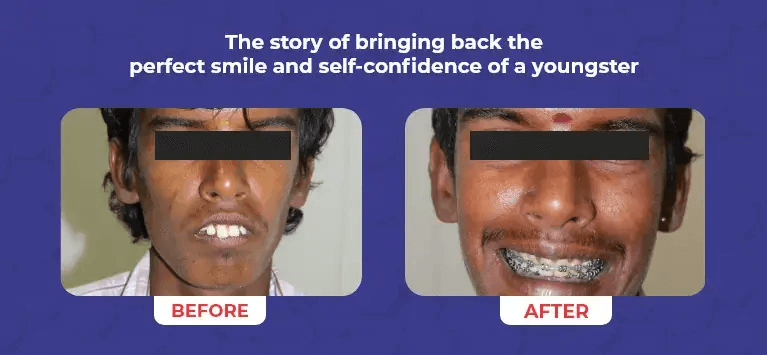

Creating Beautiful Smile

for All ages